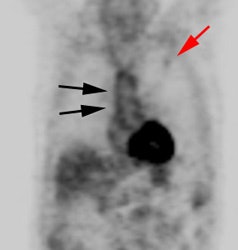

|

Normal vascular activity: Faint activity can be seen in the descending thoracic aorta (black arrows) |

Vascular graft activity: The patient below had a prior graft repair of an ascending aortic aneurysm. Tracer uptake can be seen in the ascending aortic graft (black arrows). The patient also has a left upper lobe lung cancer (red arrows). |

|